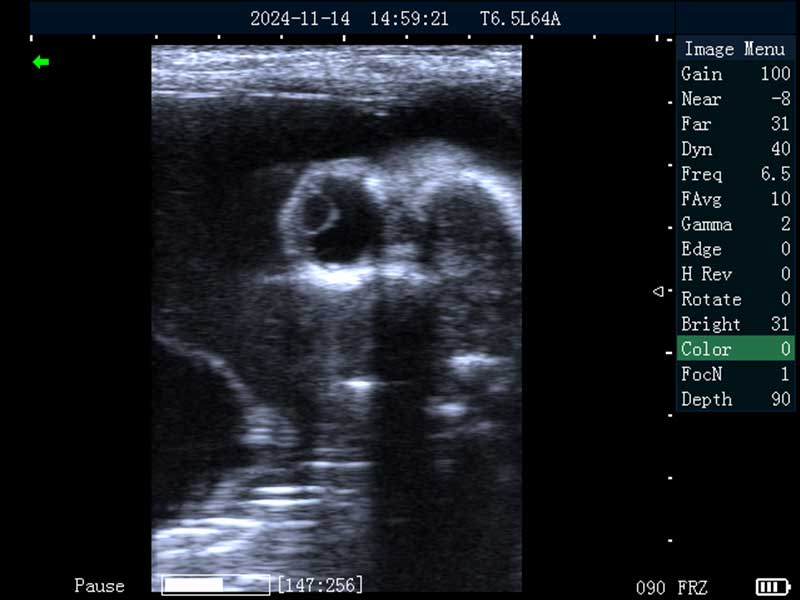

牛妊娠40日龄

牛妊娠65日龄